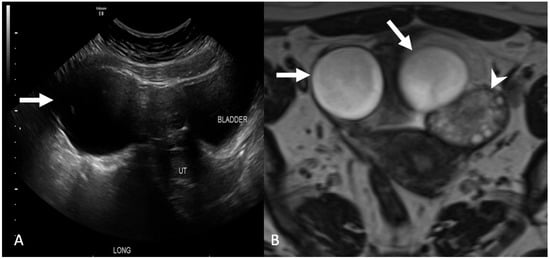

5.1.5. Paraovarian Cyst

5.1.6. Peritoneal Inclusion Cyst